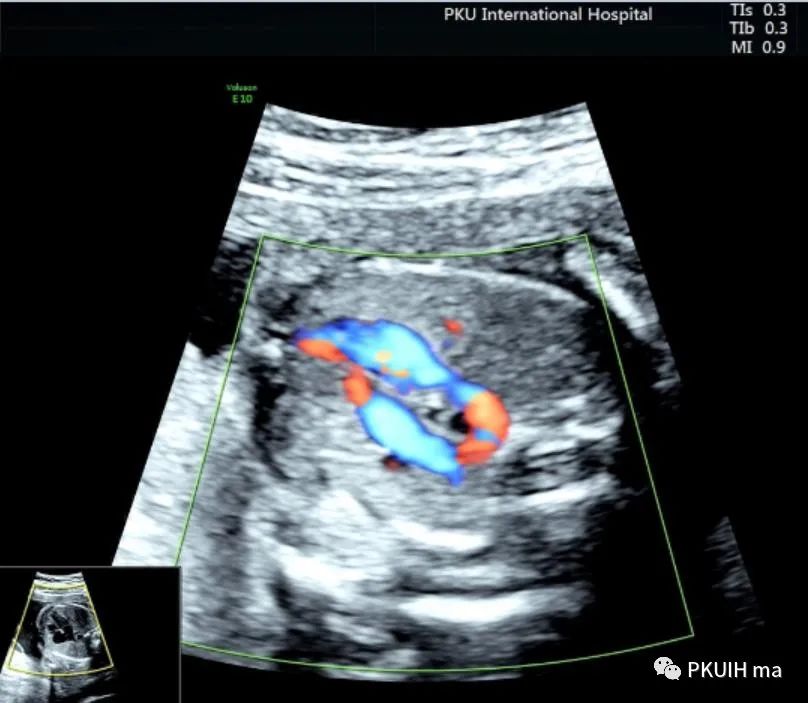

下面几张图都是右位主动脉弓、左动脉导管合并左锁骨下动脉迷走的病例,患儿出生后随访均无明显临床症状

主动脉弓走行于气管的右侧,与左位的动脉导管形成“U”型环(不完全血管环),包绕气管和食管。主动脉冠状切面可见左锁骨下动脉起自于主动脉弓降部,向左肩部走行。

右弓左导管是左位主动脉弓在左锁骨下动脉与左颈总动脉起始处之间退化,形成右弓,左位动脉导管存在于左锁骨下起源区域,右位动脉导管退化,从而形成左向右环绕气管的血管环。右位主动脉弓依次发出左颈总动脉、右颈总动脉、右锁骨下动脉及迷走的左锁骨下动脉。在个别情况下,左锁骨下动脉也可以通过Kommerell憩室的动脉管道直接起源于降主动脉。右位主动脉弓可以是复杂先心的一部分,也可以孤立存在。三血管气管切面是诊断右位主动脉弓的重要切面,结合血流显像可以鉴别右弓的三种类型。